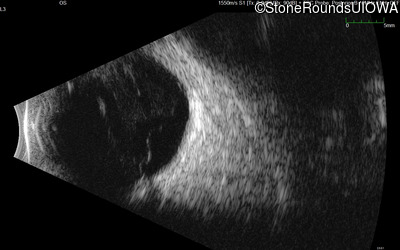

B-Scan Ultrasonography - Left - 20/40 +1

Exemplar